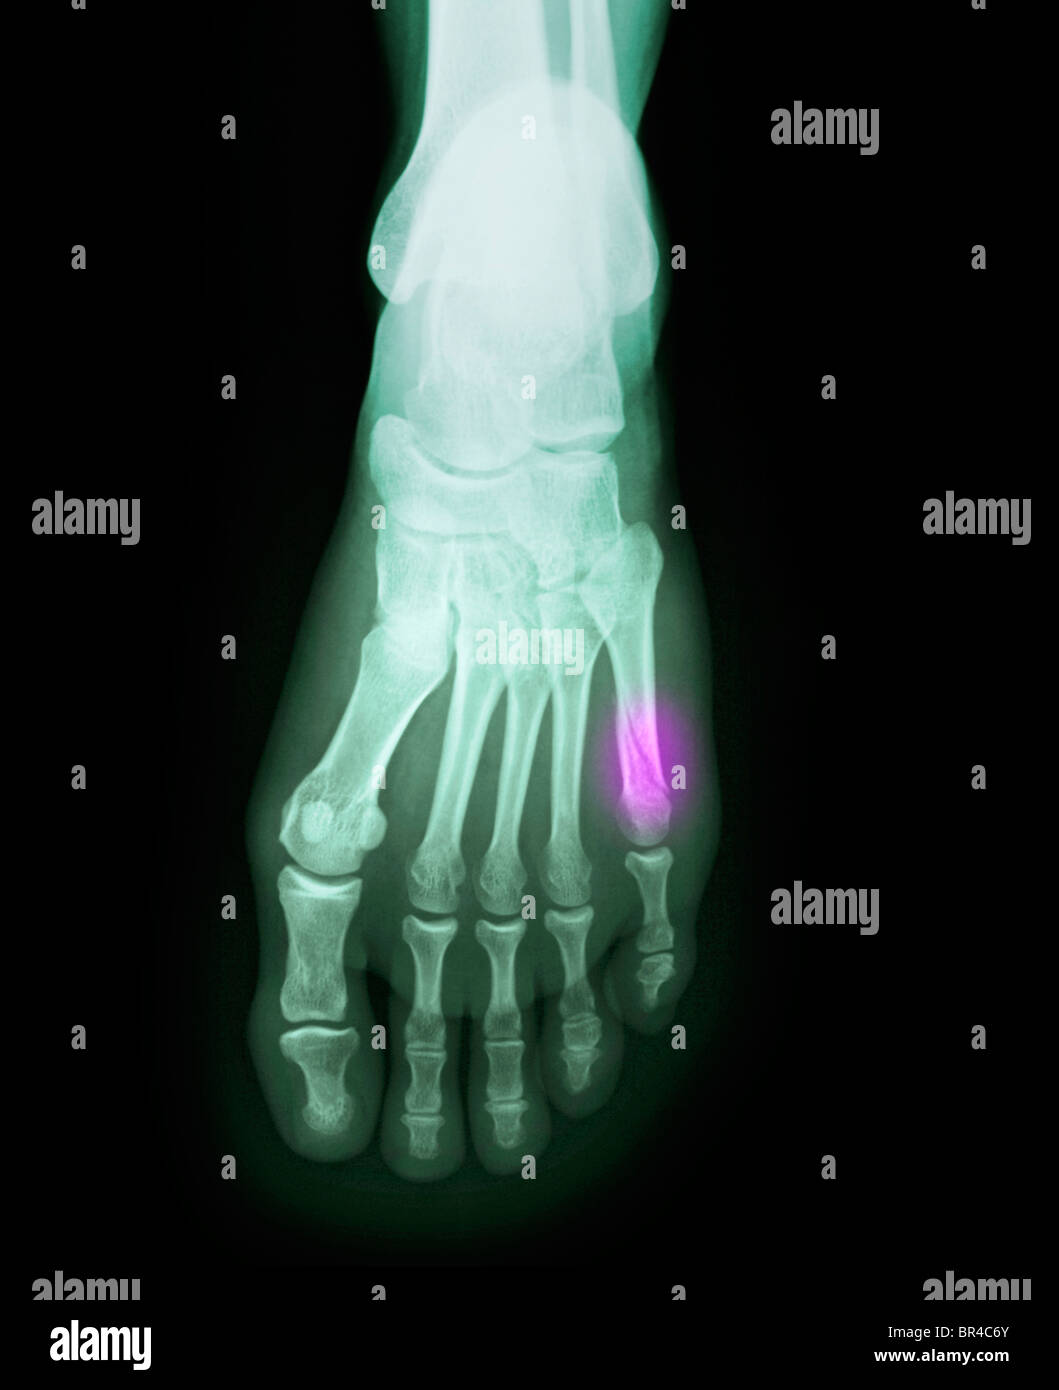

Source: atsrehabqov.pages.dev foot xray of a 37 year old female with a fractured 5th metatarsal Stock Photo Alamy , La fracture du 5e métatarse et une des fractures parmi les plus fréquentes au niveau du pied Dans certains cas, la fracture se produit plus lentement au fil du temps, car le stress sur le pied s'accumule à cause d'une utilisation répétée.

Source: cqcpsnuj.pages.dev Xray de pied avec fracture du métatarse Photo Stock Alamy , La douleur s'intensifie à la mise en charge (marche ou appui sur le pied) et lors des mouvements. Parfois, ils sont le résultat d'un traumatisme ou d'une blessure